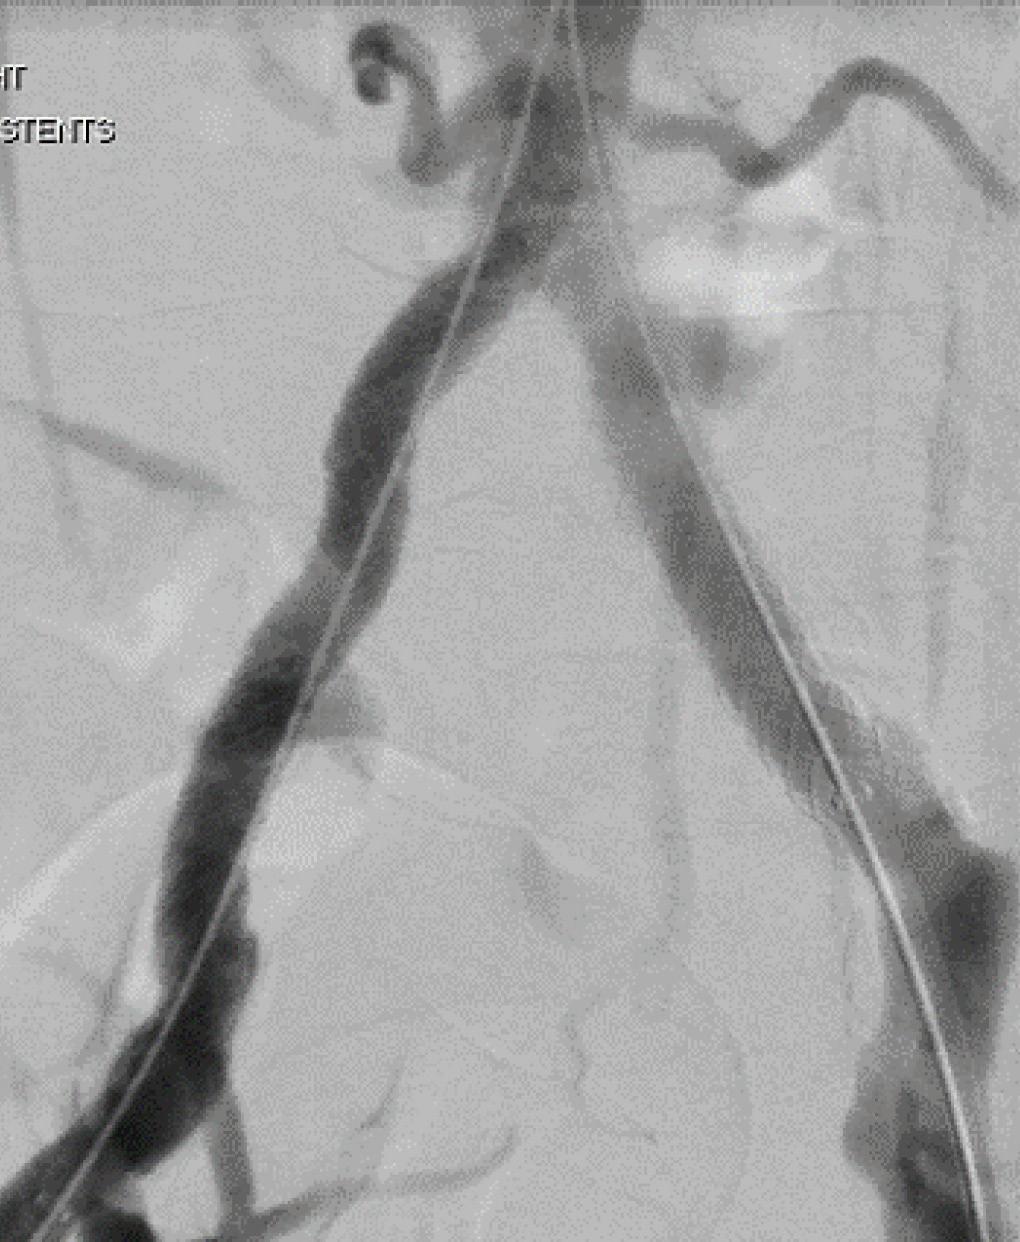

THE SAFE MANAGEMENT OF AORTOiliac graft infections has proven possible by utilizing either cryopreserved arterial allografts (CAA) or rifampin-soaked Dacron (RSD) for select in-situ reconstruction based on the findings of a recent study conducted by the Mayo Clinic and Karolinska Institutet.

Tabiei et al’s objective was to compare the safety and effectiveness of CAA and RSD as options for in-situ reconstruction in aorto-iliac graft-infected patients.

Data collected from aortic and iliac graft-infected patients undergoing in-situ reconstruction with either CAA or RSD from January 2002 through August 2022 were analyzed retrospectively to assess overall survival rates as well as secondary outcomes such as graft-related intervention, reinfection, perioperative mortality, and major morbidity,

While it was found that reinfection rates among the RSD group were lower compared to the CAA group, it was not statistically significant, making both interventions viable options for infected patients.

Although a single-center retrospective cohort study, said Tabiei, results showed “comparable early and long-term morbidity and mortality between the groups.”

VISCERAL ARTERIES PRIORITIZING

The study included 149 subjects, 80 of which received RSD intervention and 60 who underwent CAA, with a mean age of 68.9 and 69.1, respectively. Moreover, endovascular stent grafts were infected in 60 patients, 41 of which were in the CAA group, with the remaining 19 patients in the RSD group.

With respect to graft-enteric fistulas, they were significantly more common in the RSD group, and management included complete resection of the infected graft. Aortic reconstructions were covered in omentum in 57 CAA patients and 63 patients in the RSD group.

There was a median follow-up of 20.5 months in the CAA group and 21.5 months in the RSD group, with

overall survival at five years similar between the two cohorts, with 59.2% in the RSD group and 59% in the CAA group. Freedom from graft-related reintervention at one and five years was 81.3% and 66.2% in CAA patients compared to 95.6% and 92.5% in RSD patients.

Tabiei went on to describe that indications for reintervention in the CAA group included five patients with stenosis, four with pseudoaneurysm, two occlusion patients, one with graft-limb kinking, and one patient who experienced rupture.

Keith Calligaro, MD, Philadelphia: “I applaud your effort but I don’t know if we’re ever going to get a good answer on this—it’s all retrospective … I personally take a different attitude about the use of cryograft. When it's a younger patient, I tend to use the cryograft because I'm more worried about recurrent infection, but every series has shown that cryograft is more likely to develop recurrent stenosis. That's the advantage of rifampin—you're less likely to get recurrent infection.”

In the RSD group, indications for reintervention included three patients with reinfection, one occlusion patient, one endoleak patient, one with omental coverage, and one incidence of rupture. Freedom from reinfection at one and five years was 98.3% and 94.9% in the CAA cohort compared to 92.5% and 87.2% for the RSD group.

Wrapping up, Tabiei concluded that the study found both CAA and RSD to be suitable interventions, but noted that reintervention was more common with CAA—ultimately reaffirming that individualized treatment and long-term follow-up are most appropriate with aortic and iliac graft-infected patients.

Tabiei added that at his institution, CAA are considered in older patients, and in cases of highly virulent microorganisms and such instances as intra-abdominal abscesses. RSD tends to be used in younger patients and in urgent cases.